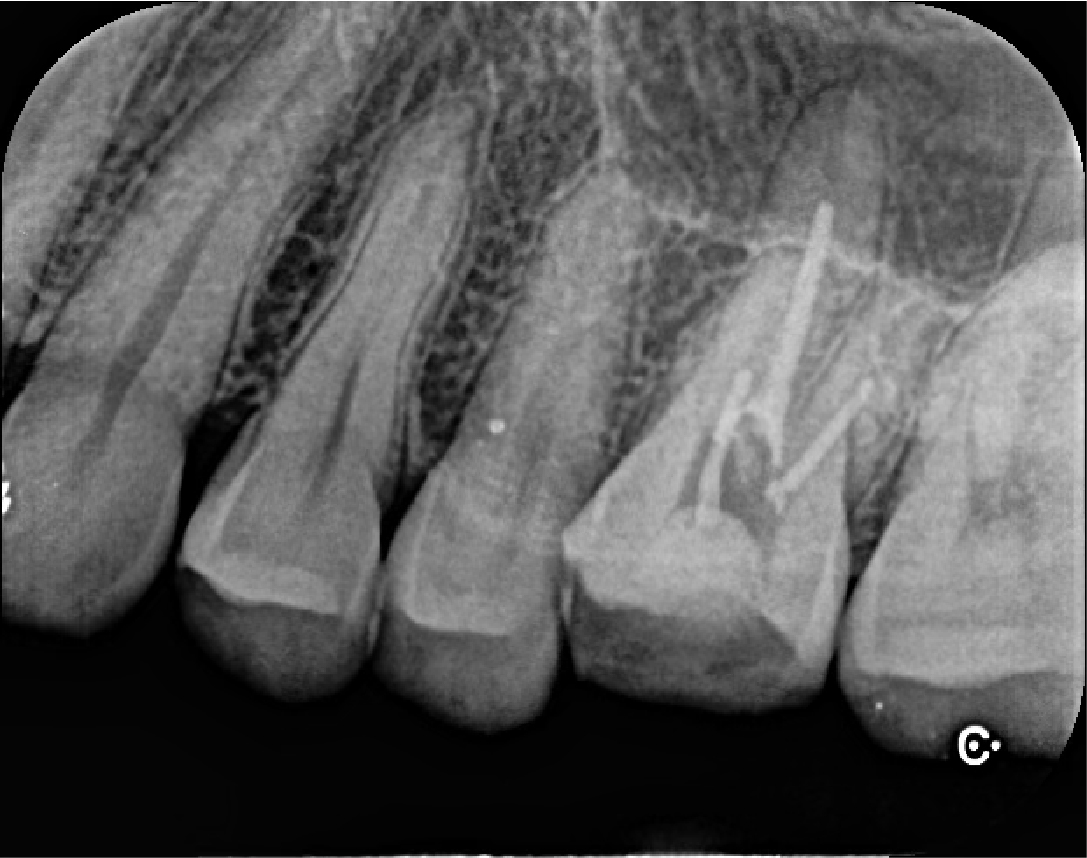

左上奥歯の強い痛みを主訴に来院されました。虫歯が大きく進行している状態でしたが、歯をしっかりと残したいとの希望から、精密根管治療を行うことになりました。2回で治療を完了し、6か月の経過観察後、かぶせものへと移行しました。術後の違和感も徐々に軽減し、良好な経過をたどっています。

| 治療内容 | 左上大臼歯の精密根管治療 |

| 治療期間 | 2回(2週間) |